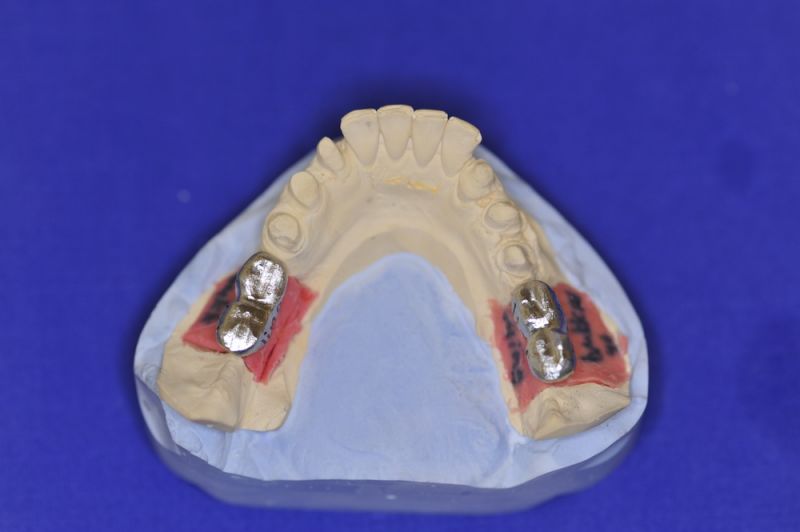

Neuromuskulär zentrierte Bisslage. Gerüste werden unbelastet durch das "Zahnfleisch" nach oben gehoben

Nun stellte sich heraus, dass der Abstand zwischen den Implantaten sehr gering war, weil die Einschubrichtungen der Aufbauten sich zum Teil gegenseitig im Wege standen. Konfektionierte Teile mussten individuell umgeschliffen werden, dabei das Ziel, den Biss korrekt einzustellen nicht aus dem Auge zu verlieren.

Heute war nun Gerüsteinprobe, mit all den Problemen der Umsetzung zwischen Laborsituation und Mundsituation. Siehe Stichpunkt "Schnittstellenproblematik"! was bei Zähnen, auf Grund deren Eigenbeweglichkeit im Kieferkochen kein Problem wäre, ist bei drei unbeweglichen Implantaten ein Riesenproblem. Darüber spricht nur in aller Regel Niemand! Es musste viel fein nachgearbeitet werden.

4 Stunden haben wir heute Temporäre Aufbauten und provisorische Kronen entfernt. Definitive Aufbauten im Munde eingeschraubt. Eine erneute Bissregistrierung durchgeführt und die Arbeit neu artikuliert. Neue Provisorien mussten auch wieder hergestellt werden.